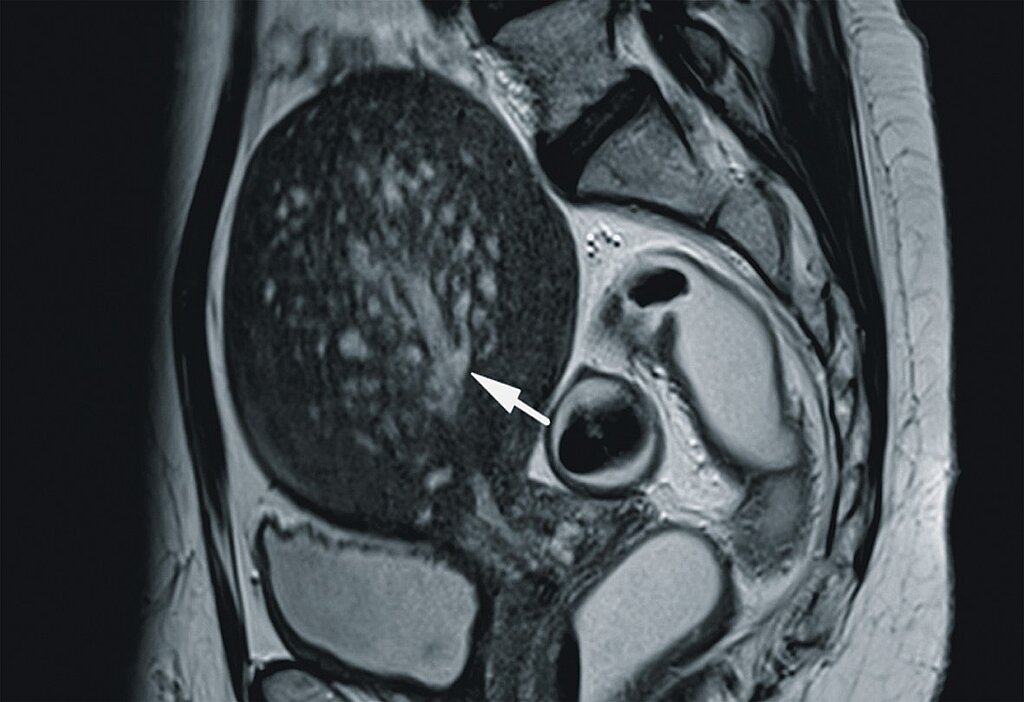

Kernspintomographie (MRT)

Bei komplexen Fragestellungen bzw. zum Ausschluss anderer Erkrankungen mit vergleichbarer Symptomatik stellt die MRT mit und ohne Distension von Vagina und Rektum ein weiteres zuverlässiges Instrument der Bildgebung dar, das Erfahrungen des Gynäkologen und des Radiologen voraussetzt [34], (Abb. 6).